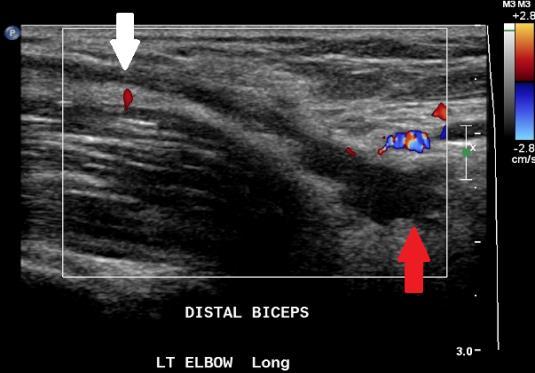

Fig. 2 Ultrasound showing normal biceps tendon (white arrows). Fig. 3 Ultrasound: The distal biceps tendon is ruptured. There is fluid and haematoma at the tendon defect (red arrow), and the tendon is retracted proximally (white arrow).

Fig. 4 Ultrasound showing biceps tendon retraction causing bunching and thickening of the torn tendon stump.

Ultrasound

Can confirm the tendon rupture and locate the tendon remnant

Fluid or haematoma may be seen in a measurable tendon gap

On ultrasound the very distal attachment to the tuberosity may be difficult to visualise due to the oblique tendon path. Determining the grade of